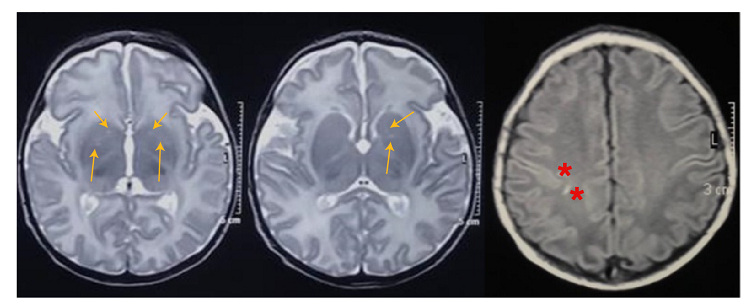

Otros hallazgos en el curso de la hospitalización incluyeron la disminución de la amplitud y de la frecuencia de movimientos espontáneos, falta de fijación y seguimiento visual, ausencia del reflejo nauseoso, succión lenta y descoordinada e hipotonía generalizada persistente. En la resonancia magnética realizada a los 12 días del nacimiento, se evidenciaron lesiones de los ganglios basales y subcorticales derechas secundarias a hipoxia sin lesión hemorrágica (figura 1), en tanto que, en el estudio polisomnográfico basal, se registró actividad epileptiforme focal frontal izquierda y temporal bilateral. También, se reportaron potenciales evocados visuales anormales por ausencia de la banda P, sugestivos de lesión prequiasmática o cortical.

Acorde a la presencia de hallazgos estructurales, el paciente presentó anormalidades en las neuroimágenes (lesiones en los ganglios basales y subcorticales derechas secundarias a la hipoxia). Asimismo, se reportó un electroencefalograma anormal en concordancia con la aparición de convulsiones, lo que se ha asociado con resultados adversos en múltiples estudios 15,16. Sin embargo, en este paciente no hubo convulsiones después del periodo neonatal.